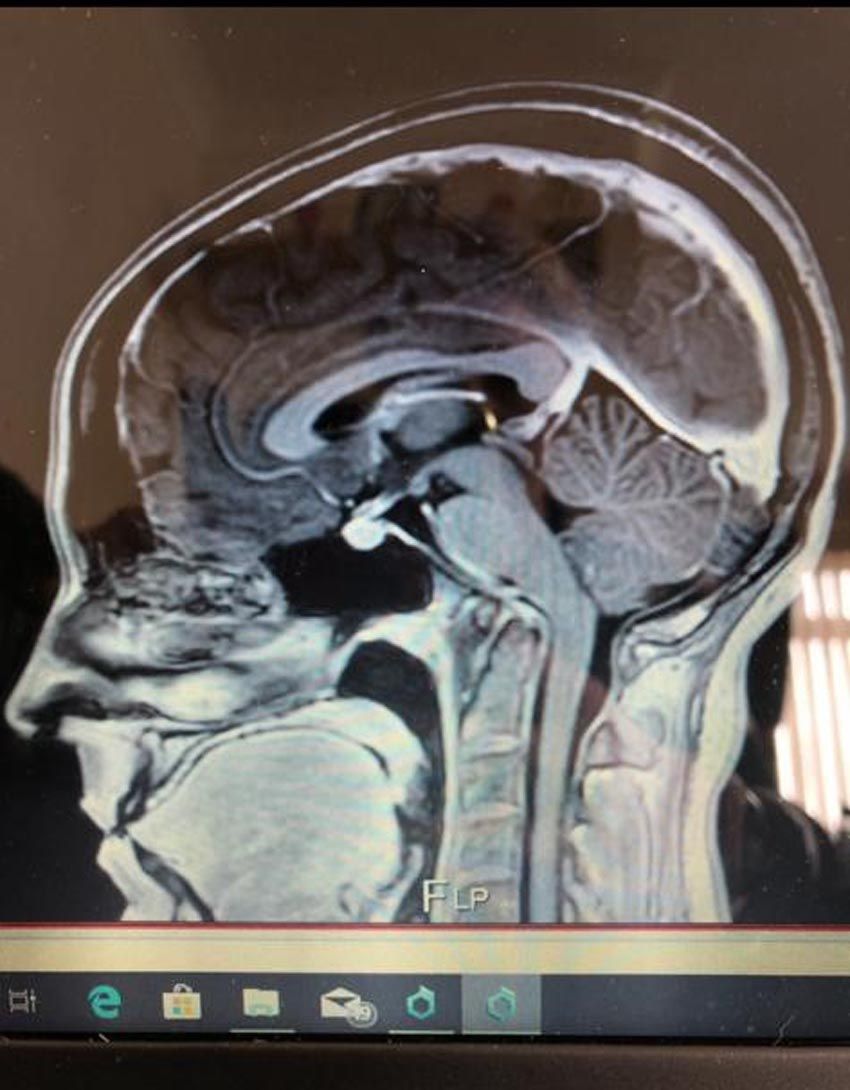

Seeing a private endocrinologist – a specialist treating problems with hormones – in the autumn of 2018, she had an MRI scan, which came back clear.

And in May 2019, a neurologist also diagnosed her with Chiari malformation, a non-life threatening condition, where the lower part of the brain pushes down into the spinal canal, according to the NHS.

Then paying £1,300 ($1,570) for a private upright MRI scan, Rachel asked for the images be sent to Dr. Gilete, a top neurosurgeon she had found via a Facebook group in Barcelona, Spain – one of only three experts worldwide dealing with minimal invasive spinal surgery techniques.

Having assessed the MRI and carried out a detailed questionnaire, he added to her diagnosis atlantoaxial instability – where the vertebrae holding her skull in place become unstable and dislocated, hydrocephalus, which is an accumulation of cerebrospinal fluid within the brain, scoliosis, a curvature of the spine, and cervical medullary syndrome, which is caused by brain stem compression.